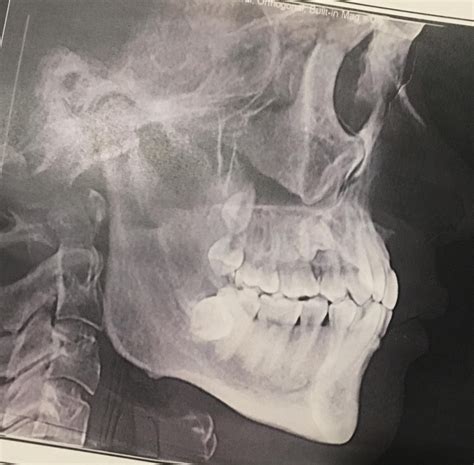

Many individuals seek facial rejuvenation or structural correction to achieve a more balanced aesthetic, and for those dealing with a vertically deficient lower third of the face, Short Face Syndrome surgery often provides the definitive solution. This condition, medically referred to as skeletal deep bite or vertical maxillary deficiency, occurs when the upper jaw is underdeveloped vertically, leading to a crowded smile, a diminished chin profile, and the appearance of premature aging. Understanding the surgical interventions available is essential for anyone considering a transformation that addresses both function and facial harmony.

The primary medical intervention for this condition is orthognathic surgery, specifically a Le Fort I osteotomy. When people research Short Face Syndrome surgery, they are often looking for how a surgeon moves the maxilla (upper jaw) into a more favorable position. By surgically repositioning the jaw vertically, the surgeon increases the height of the lower face, which improves tooth display and creates a more balanced aesthetic profile.

1. Comprehensive Consultation: Digital imaging, including 3D CT scans, is used to map the facial structure and determine the exact movement needed.